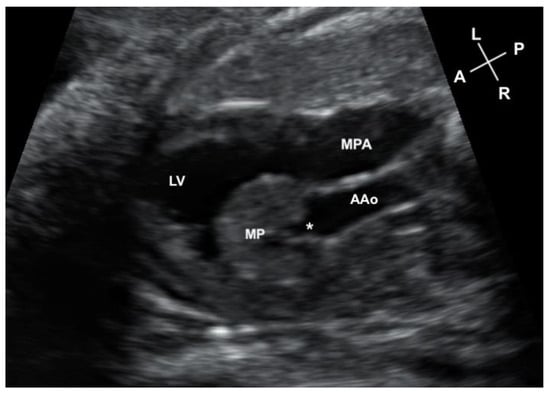

Figure 1.

Axial image on the fetal scan of the myocardial pouch (MP) protruding into the left ventricular cavity (LV) and the connection of the pouch (*) to the ascending aorta (AAo). The main pulmonary artery (MPA) is seen to the left of the ascending aorta.